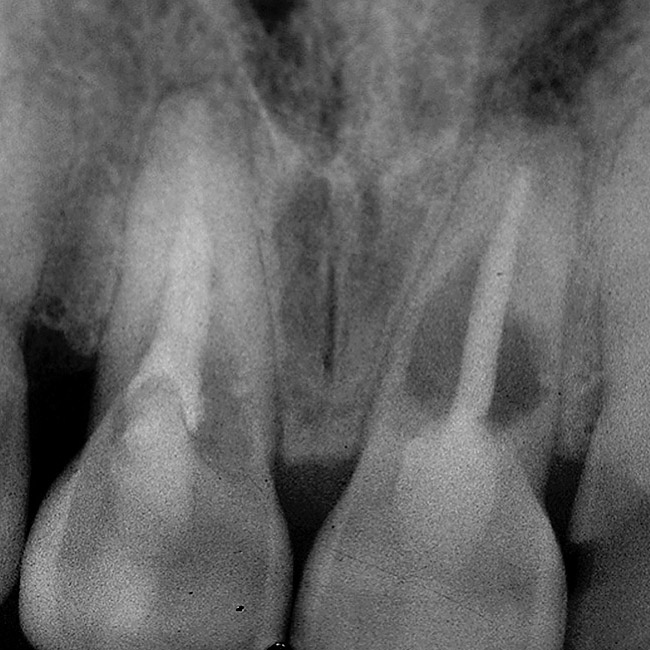

Figure 10  In these adjacent implants placed in the central and lateral positions, note the excellent interproximal bone but minimal interimplant distance.

Figure 10

Figure 11  Soft-tissue levels were acceptable at the time of placement of the final restoration.

Figure 11

Figure 12  At 6 months postinsertion, the papilla receded as bone was lost.

Figure 12

Figure 13  Twelve months after placement, soft tissue migrated apically as bone between the implants continued to resorb.

Figure 13